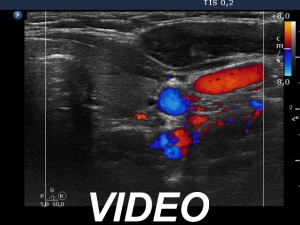

Ultrasonography. The thyroid was echonormal or minimally hypoechoic. There was a moderately hypoechoic nodule which had a cystic portion in the lower part. The nodule had lobulated margins and contained different hyperechoic figures. Beside figures caused either by posterior enhancement of proliferation of connective tissue, several ambiguous. bright granules were also found. Compared with the first measurement, the nodule is increased by more than 75% in volume.

Comment. It is worth looking at the video several times and analyzing the various echogenic foci.